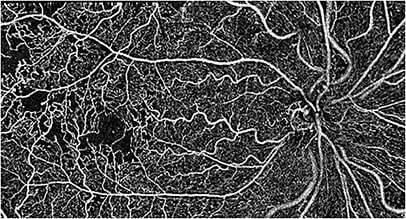

A montage image taken of a 54-year-old diabetic Black female who has reduced vision and a BCVA of 20/40 OD. The image was captured using Visionix’s Optovue Avanti, with the AngioVue software.